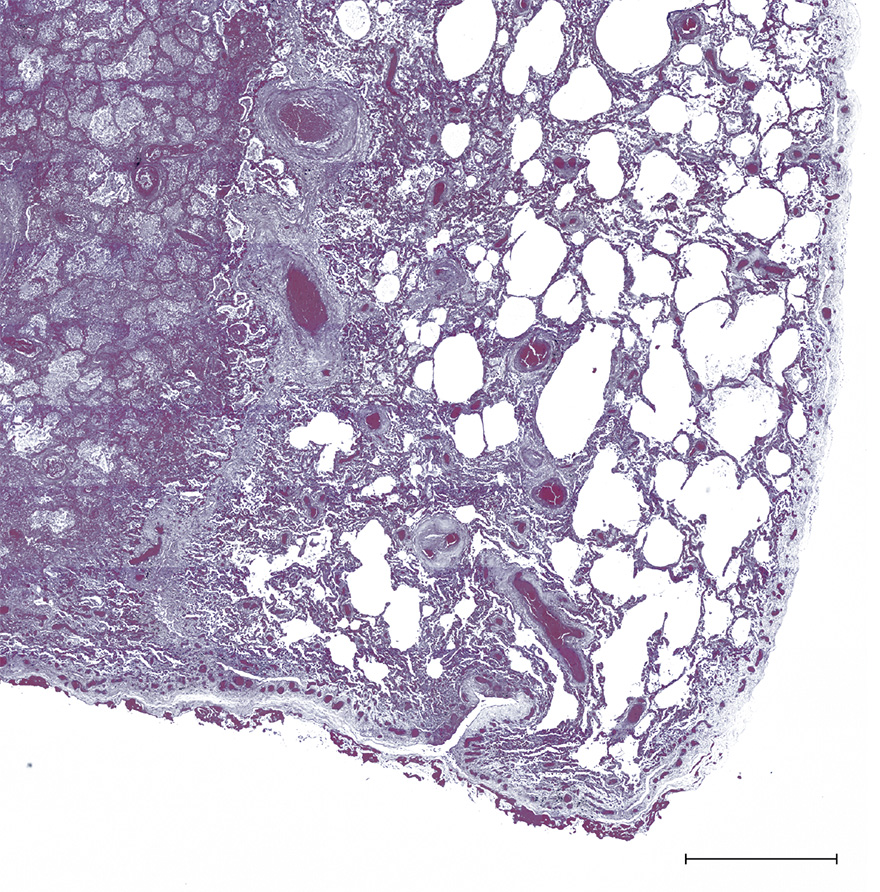

Figure 6 An area of necrosis in the lung caused by blockage of the blood supply is visible on the left of this section. The area on the right includes surviving lung tissue, which is thickened and has areas of fibrosis. Scale bar = 2 mm.

2 Cell death and degeneration